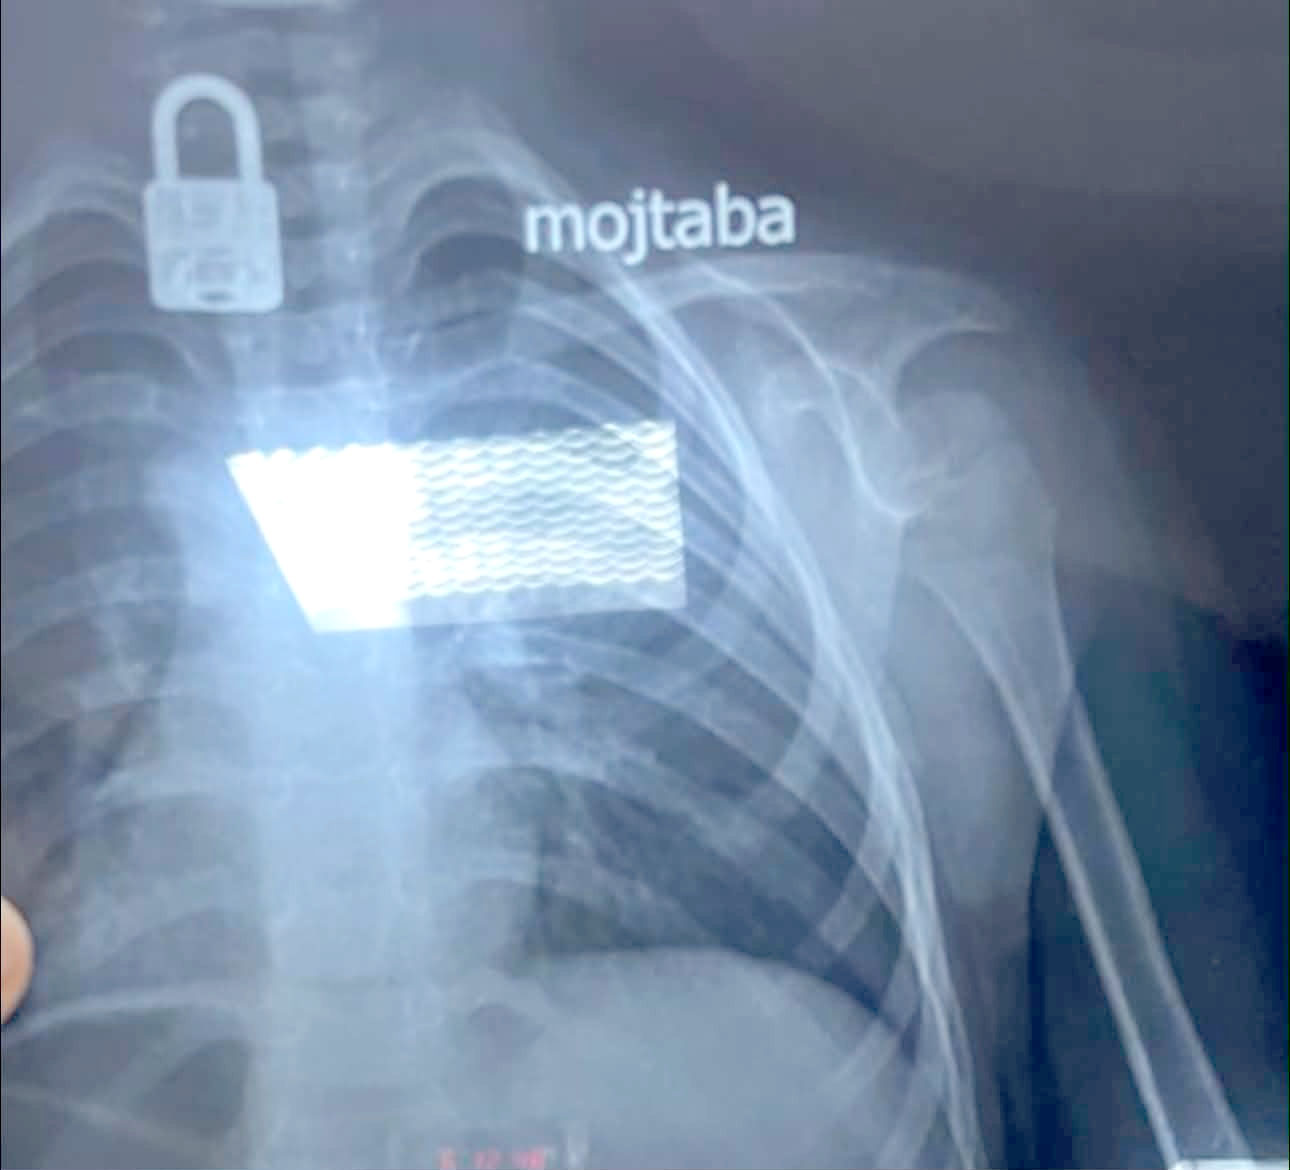

النجف: إستخراج قفل إبتلعه طفل بعمر 4 سنوات

نجح فريق طبي بمستشفى الزهراء التعليمي التابع لدائرة صحة النجف، في استخراج قفل من جسم طفل يبلغ من العمر أربع سنوات. وقال بيان تلقته (الزمان) أمس إن (قسم جراحة الأطفال استقبل حالة طارئة لطفل يبلغ من العمر أربع سنوات بعد ابتلاعه جسماً غريباً). وأضاف إنه (بعد إجراء فحص بالأشعة السينية تبين وجود قفل داخل جسم الطفل، وعلى إثر ذلك تم التنسيق مع مدينة الصدر الطبية وتحديداً قسم جراحة القلب والأوعية الدموية لاستخراجه). وتابع البيان إنه (تمت العملية بنجاح عبر الناظور، وإن الطفل يتمتع حالياً بحالة صحية جيدة). فيما أكد مصدر طبي، وفاة طفلة حديثة الولادة وإدخال والدتها إلى العناية المركزة، إثر خطأ في نقل فصيلة الدم داخل أحد مستشفيات ذي قار. وقال المصدر أمس إن (امرأة في العشرينات من عمرها أُدخلت إلى وحدة الولادة في مستشفى الحبوبي وسط مدينة الناصرية، وكانت حالتها الصحية تستدعي نقل دم من فصيلة، إلا إنه تم تزويدها بدم من فصيلة أخرى). مؤكداً إن (المريضة وضعت طفلتها، التي توفيت بعد نحو ساعة من الولادة). مبيناً إن (الأم لم تتوفَ نتيجة تلقيها سابقاً علاجات خاصة بحالات عدم توافق فصائل الدم، لكنها تعرضت لمضاعفات خطيرة أدت إلى تدهور حالتها الصحية). وأشار إلى إن (الأم نُقلت لاحقاً إلى المستشفى التركي وأُدخلت وحدة الإنعاش، بعد تعرض بعض أعضاء جسدها لمضاعفات حادة نتيجة نقل الدم غير المطابق). وشدد على القول إن (الجهات التحقيقية باشرت في فتح تحقيق موسع للوقوف على ملابسات الحادث وتحديد المقصرين).